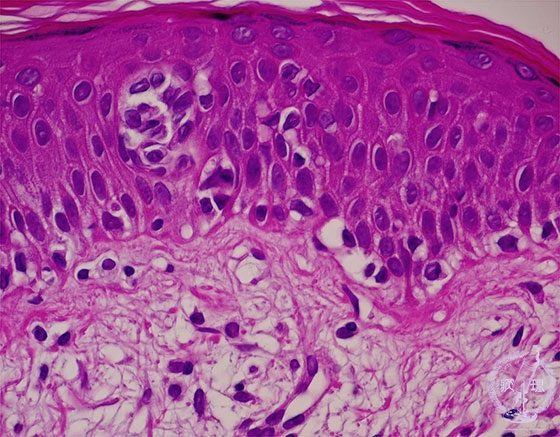

- (11)Malignant lymphoma of the skin (Mycosis fungoides)

Atypical lymphocytes infiltrate the epidermis with a microabscess (inside a circle).